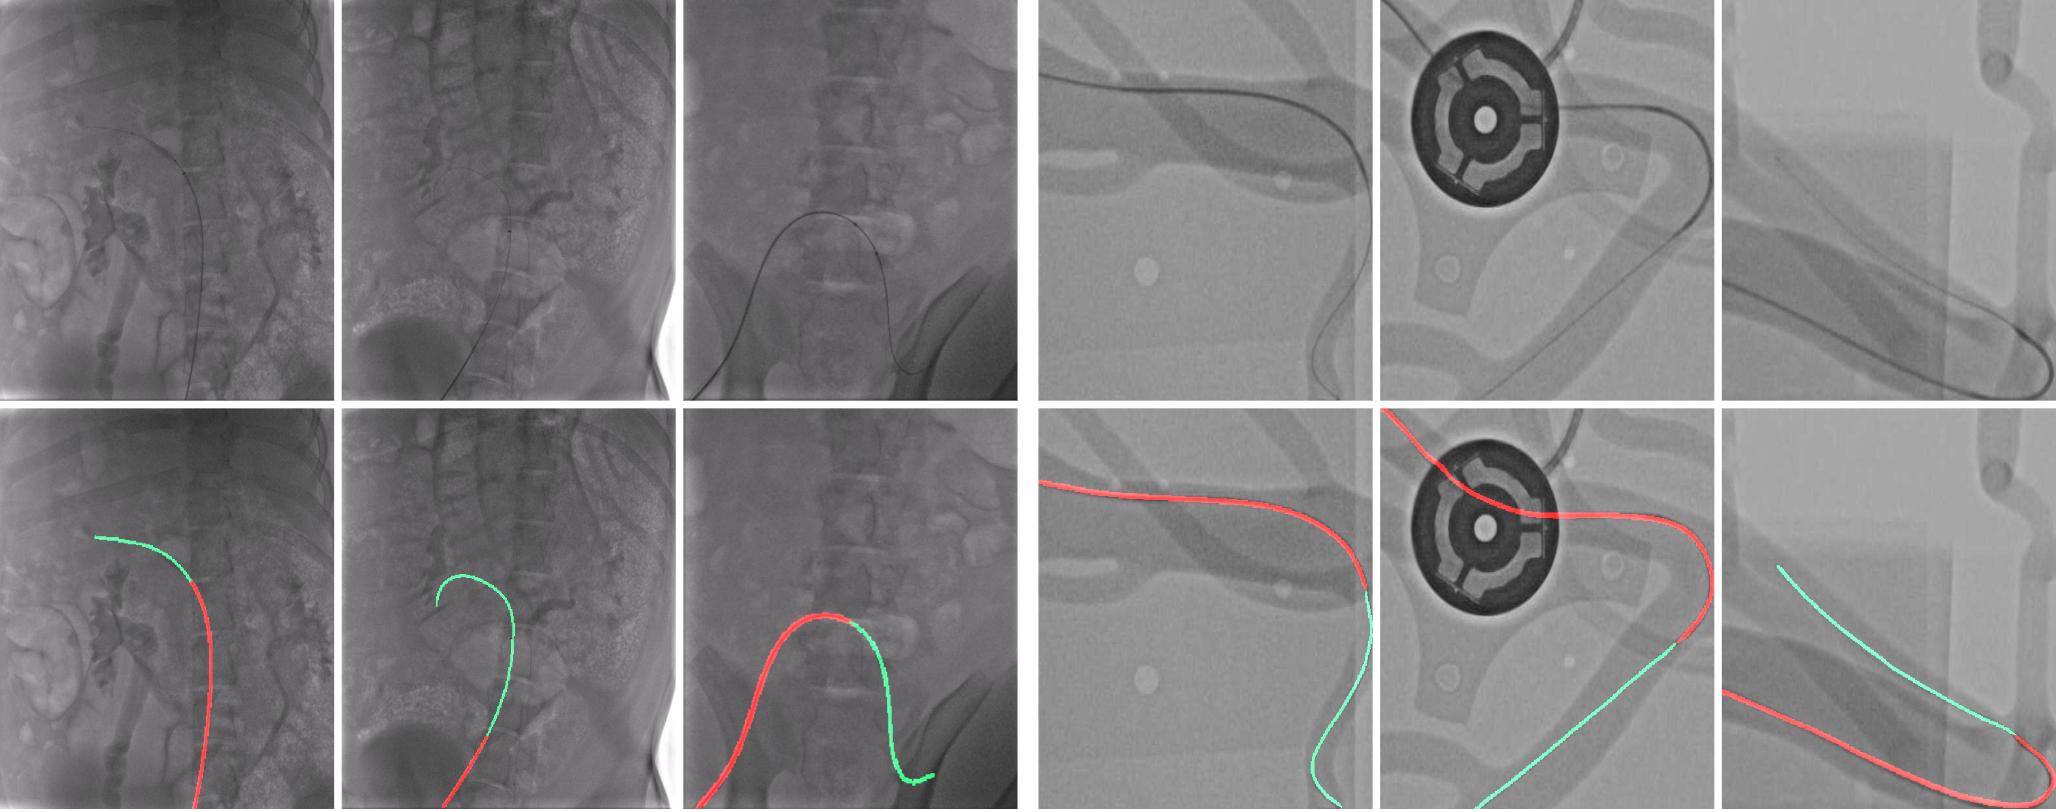

Refer to caption

Figure 1: Catheter and guidewrite segmentation in X-ray images. First row: The input X-ray images. Second row: The segmentation results. Red color denotes the catheter, green color denotes the guidewire.